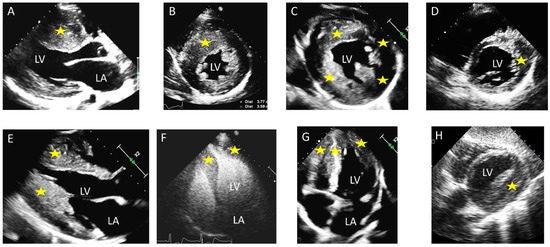

| Echocardiography | Septal hypertrophy; LVOT obstruction; SAM of the anterior mitral leaflet ± SAM-associated mitral regurgitation | Uniform thickening of LV walls; no LVOT obstruction typically | Apical wall thickening; “ace-of-spades” morphology of the LV cavity; ±apical aneurysm |

| CMR Findings | Asymmetric septal hypertrophy; LGE at RV insertion points and patchy LGE at the site of maximum hypertrophy | Symmetrical hypertrophy with variable patterns of LGE | Apical cavity systolic obliteration, loss of apical tapering; an apical aneurysm ± apical LGE and/or thrombus may be present |